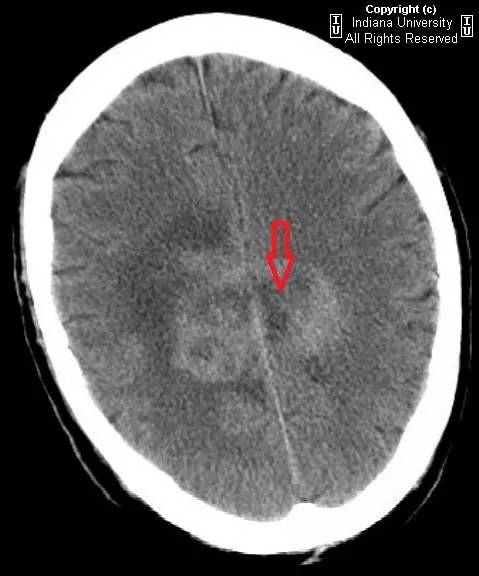

图 2 平扫 CT,病变蔓延进入双侧半卵圆中心(红色箭头),右侧明显

可见一中心位于胼胝体压部的占位性病变,密度不均,中心为低密度,周围环状水肿。推压双侧脑室。右侧侧脑室室管膜极有可能受累。占位蔓延进入双侧半卵圆中心,右侧明显。MR 上,病灶成周边强化,中央无强化低信号表明有坏死性改变。